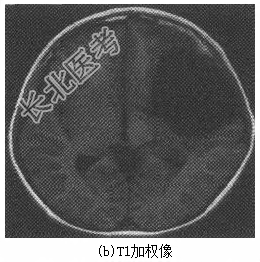

患儿男性,9岁。因“反复头痛半年,加重1天”入院。缘于入院前半年无明显诱因出现阵发性头痛,以左侧颞部明显,呈闷痛样性质,未向他处放射,每次持续约数分钟至半小时不等,尚可忍受,休息后可缓解,无发热、呕吐、四肢抽搐,无偏瘫、失语、智力异常等,未重视未诊治。1天前上述症状加重,部位及性质同前,发作更为频繁,无法正常学习、生活。病程中,食欲尚可,二便正常。体格检查T36.7℃,P98次/min,R20次/min,BP96/58mmHg。神志清楚,言语清晰,对答可,记忆力、定向力、反应力正常。头围54cm,头颅外观无畸形。双侧瞳孔等大等圆,直径约3.0mm,对光反应灵敏,双眼各向活动正常。双侧额纹对称,口角无歪斜,伸舌居中。颈软,心肺腹部查体无明显异常,四肢肌力及肌张力正常,双侧病理征阴性,脑膜刺激征阴性,小脑征阴性。辅助检查头颅CT平扫(图6-38)提示左侧颅中窝蛛网膜囊肿。头颅MRI平扫(图6-39)提示左侧颅中窝占位性病变,大小为8.0cm×6.5cm×6.4cm,考虑蛛网膜囊肿。

图6-39头颅MRI治疗完善术前准备,包括三大常规、凝血功能、肝肾功能、电解质检测,完善心电图、胸部X线片、腹部超声等常规术前评估。除了上述常规的外科术前检查以外,还有如下专科检查和处理。(1)脑电图未见明显脑电异常。(2)眼科检查测眼压10mmHg(眼压计测量法)。(3)腰椎穿刺术颅内压130mmHg,脑脊液常规及生化正常。(4)予以在全麻下行蛛网膜囊肿造瘘术。